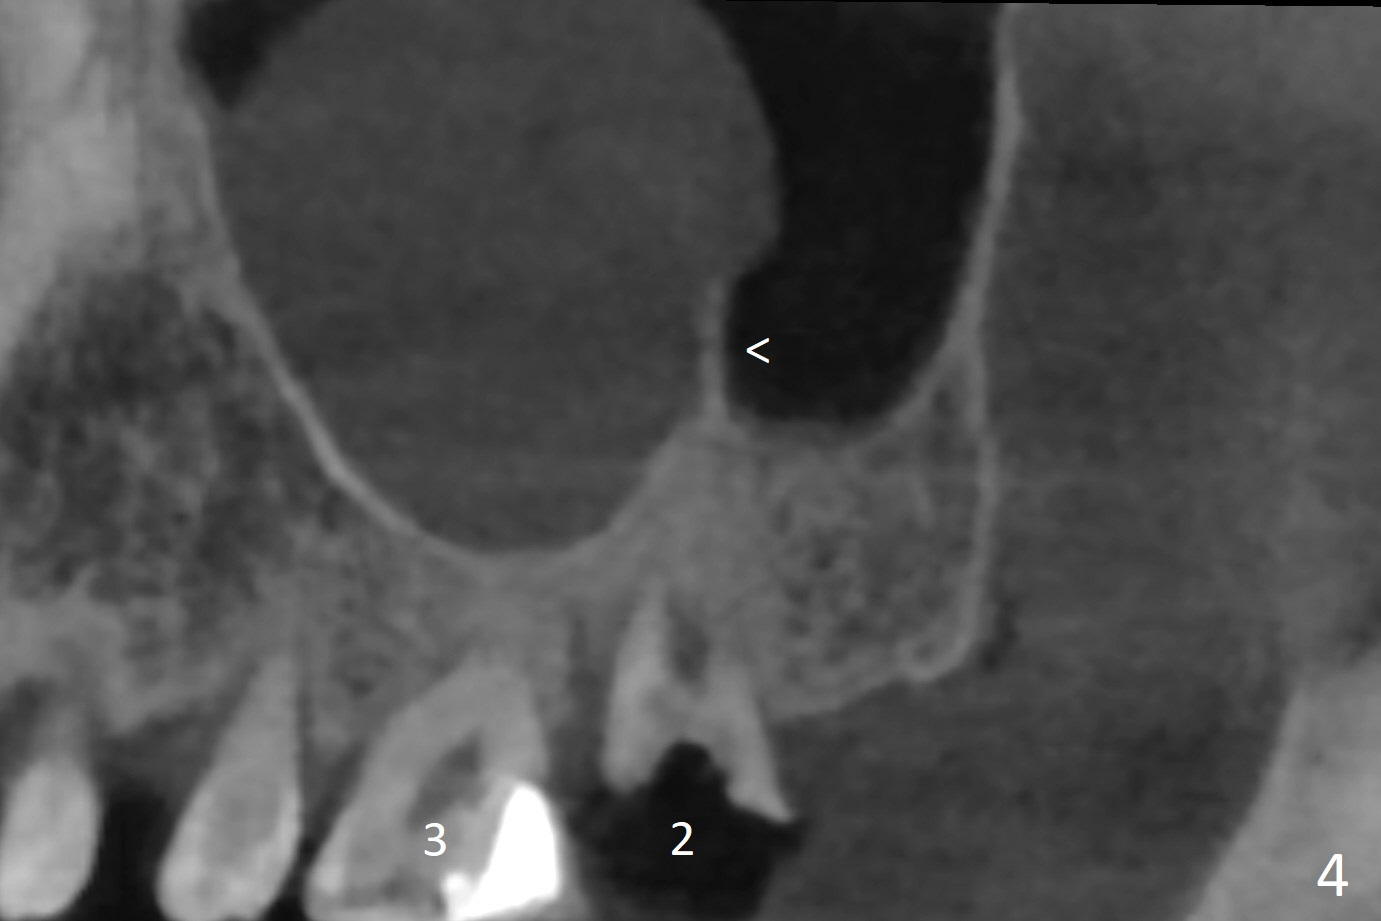

A 51-year-old man agrees to have #2 residual root to be extracted for implant. Panoramic X-ray (Fig.1) and CT coronal section (Fig.2) show maxillary sinus mucocele (*). A 5x10 mm implant will be placed not to intrude into the sinus (Fig.2,3). In case sinus membrane perforation, prepare PRF membranes for repair. The apex of the implant will be engaged to an apparent sinus septum for stability (Fig.4,5,7 arrowheads). Fig.4,5,6 are sagittal and coronal sections and 3-D image of Fig.3 without an implant at #2, while Fig.7 is the inferior view of Fig.6 (arrow).